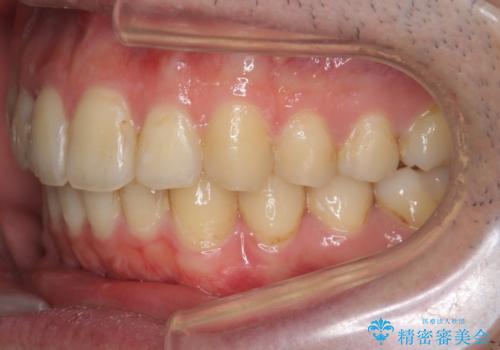

奥歯のかみ合わせを特に変えず、前歯の並びを整える治療をおこないました。

奥歯のかみ合わせは1本分ずれているとはいえ、1歯対2歯の交互のかみ合わせになっているため、そのままにしてもそこまで大きなデメリットはありません。

右上のかみ合わせをそのままにするため、上下の正中は合わない仕上がりとなります。

今回は右のかみ合わせはそのままにしました。左は特に初めから問題ない状態でした。

右のかみ合わせを変えず部分矯正にしたことによって、治療が短期間で済み、また、ワイヤーでなくインビザラインで治療が可能、歯も抜かなくて済むなどメリットの多い方法であるといえます。